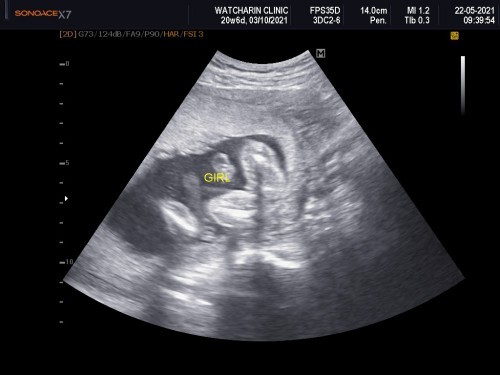

ซาวตอน20week หมอบอกเป็นผู้หญิง ใจแม่ก็อยากได้ผู้หญิงค่ะ แต่คนชอบทักว่าน่าจะผู้ชาย เคยมีแม่ๆบ้านไหนผลซาวคาดเคลื่อนหรือผิดเพศบ้างมั้ยค่ะ ขอคำแนะนำหน่อยค่ะ

เหมือนกันค่ะ ท้องน้องผญ ซาวน์เป็นหญิง แต่คนส่วนใหญ่ชอบทักว่าผู้ชาย เพราะท้องใหญ่ยื่น และหน้าไม่เนียนสวยผุดผ่อง แต่เราเชื่อหมอค่ะ มั่นใจ100% เพราะหมอซาวนเห็นอวัยวะน้องชัดเจน คนอื่นดูด้วยตาเปล่า มองทะลุท้องก็ไม่ได้ จะทราบได้อย่างไร แถมมั่นใจบอกหมอซาวน์ผิดด้วย ผลสรุป คลอดน้องผู้หญิงค่ะ

ผู้หญิงค่ะคุณแม่ยินดีด้วยค่ะส่วนคนที่ทักนี้ทักตามประสาคนที่คิดไปเองด้วยการดูจากท้อง จากผิวพรรณ ซึ่งมันไม่สามารถระบุได้ค่ะ ต้องอัลตราซาวด์,ตรวจโครโมโซม ,เจาะน้ำคร่ำถึงจะรู้ผลที่แน่นอนค่ะ (อย่าไปใส่ใจค่ะ)

บ้านนี้หมอบอกว่าถ้าผู้ชายคือเห็นไข่เห็นจู๋แล้วค่ะ ชัดเจน100% ส่วนความคลาดเคลื่อนในส่วนที่เห็นเป็นผู้หญิงตอนแรกอาจหนีบไว้มีความคลาดเคลื่อนได้ค่ะ

น้อยมากค่ะแม่จะพลาด บ้านนี้ตรวจ Nifty+ซาวด์ได้ผช. แต่คนทักมาตลอดว่าได้ผญ. 20 week นี่ชัดเจนมากเลยนะคะแม่